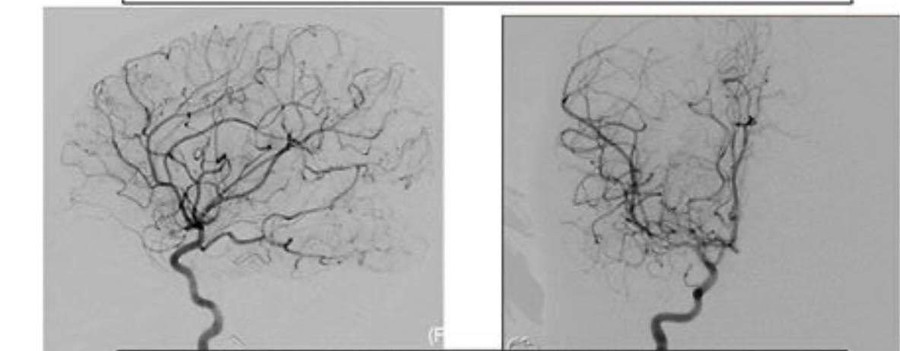

Hình ảnh động mạch sau khi được can thiệp.